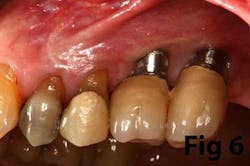

Fig. 6: Implants placed in lateral window sinus graft with no augmentation of attached tissue.